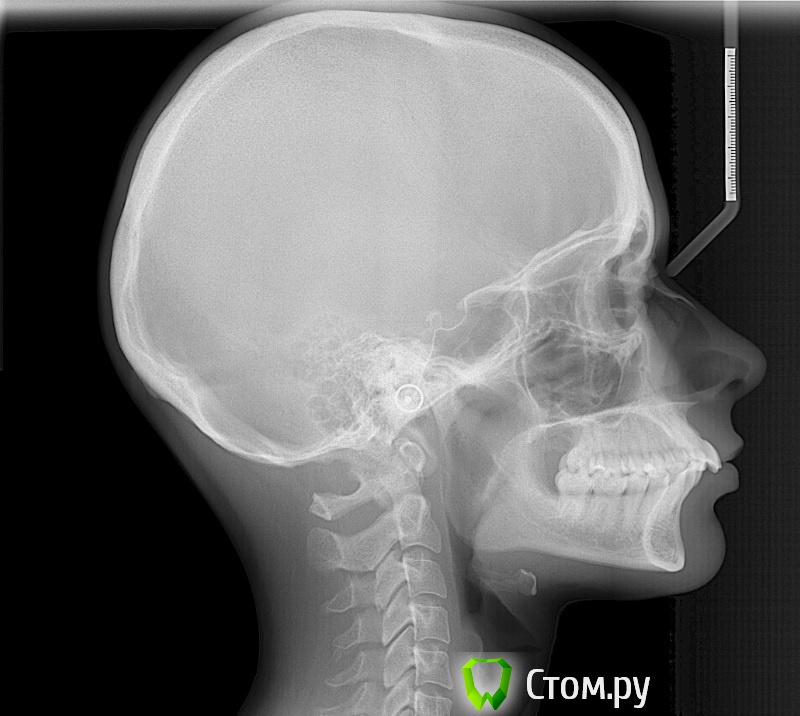

Tirend Опубликовано 25 ноября, 2013 Поделиться Опубликовано 25 ноября, 2013 Добрый день!Собираюсь ставить брекеты. Ходила на консультации к 5 разным ортодонтам. В двух местах предложили просто сразу ставить брекеты, дополнительно зубы удалять не надо (у меня уже удалены все 4 зуба мудрости), нужна будет только сепарация . Ещё в двух местах предложили поставить брекеты ( сначала на верхнюю челюсть, потом через неcколько меcяцев на нижнюю), пока без удаления, через год примерно смотреть ситуацию и тогда решать вопрос об удалении четвёрок, также возможно потребуется установка ортоимплантов в случае удаления. В последнем месте врач пощупала челюсть при смыкании, сказала, что обязательно нужна сплинт-терапия, т.к. нижняя челюсть "ходит". Что у меня смещение центра, об этом говорили все врачи, но сплинт предложили только в одной клинике. Ношение сплинта в течении 3 месяцев круглосуточно, потом обязательное удаление зубов перед установкой брекетов, сколько зубов под удаление - решаться будет только после сплинтов. При жевании щелчков вроде бы нет, болей тоже не замечала. Теперь думаю, нужно ли мне это - ведь это лишние денежные траты и время, хотелось бы уже поскорее начать основное лечение. Также все врачи замечали сужение обеих челюстей, дистальный прикус, экстремальный наклон зубов. Стоит ли пройти сплинт-терапию и сразу удалить зубы перед фиксацией брекетов или лучше начать лечение без удаления и решать этот вопрос в процессе? Ссылка на комментарий